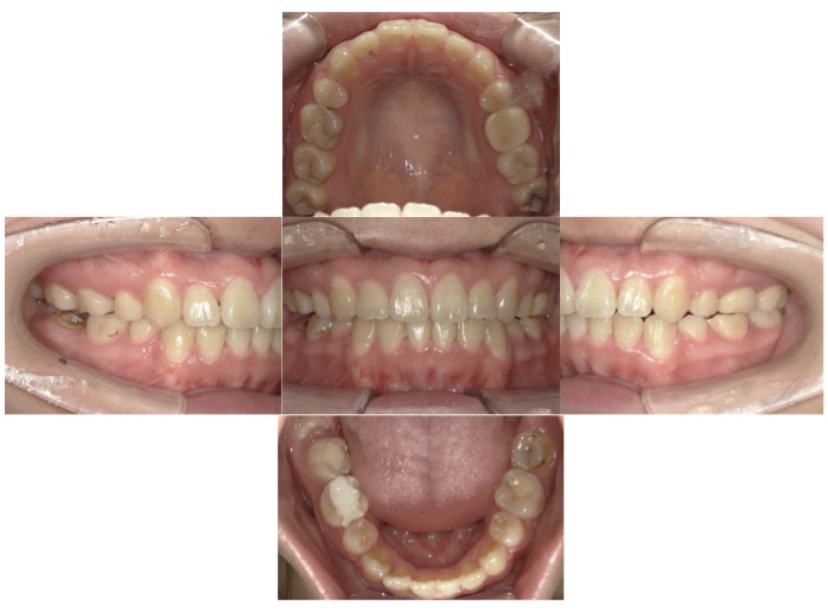

症例4

下顎前突、叢生

抜歯

ブラケット矯正

上下顎叢生、反対咬合(上下の前歯のガタガタ、若干受け口)のケースです。

装置はラビアル(上下表側)で、上下顎の小臼歯を4本抜歯を行っています。抜歯したスペースを使って、上下の叢生改善と前歯の受け口の改善を行っています。

主訴 前歯のガタガタを治したい。

年齢・性別 45歳 女性

お住まいの地域 神奈川県川崎市

治療方針 抜歯スペースを利用して上前歯の叢生(ガタガタ)の改善と受け口の改善

抜歯部位 上顎左右第一小臼歯、下顎左右第二小臼歯

使用装置 ラビアル(上下表側)、顎間ゴム

治療期間 2年6か月

治療回数 20回

リテーナー クリアリテーナー

BEFORE